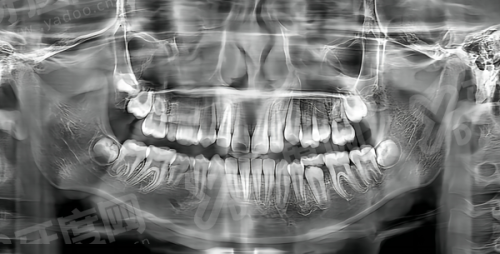

1、精良诊疗设备:医院配备了一系列精良的口腔诊疗设备,如数字化口腔CT、口腔内窥镜、超声波洁牙机等,这些设备能够更精细地诊断病情,提高治疗成效。